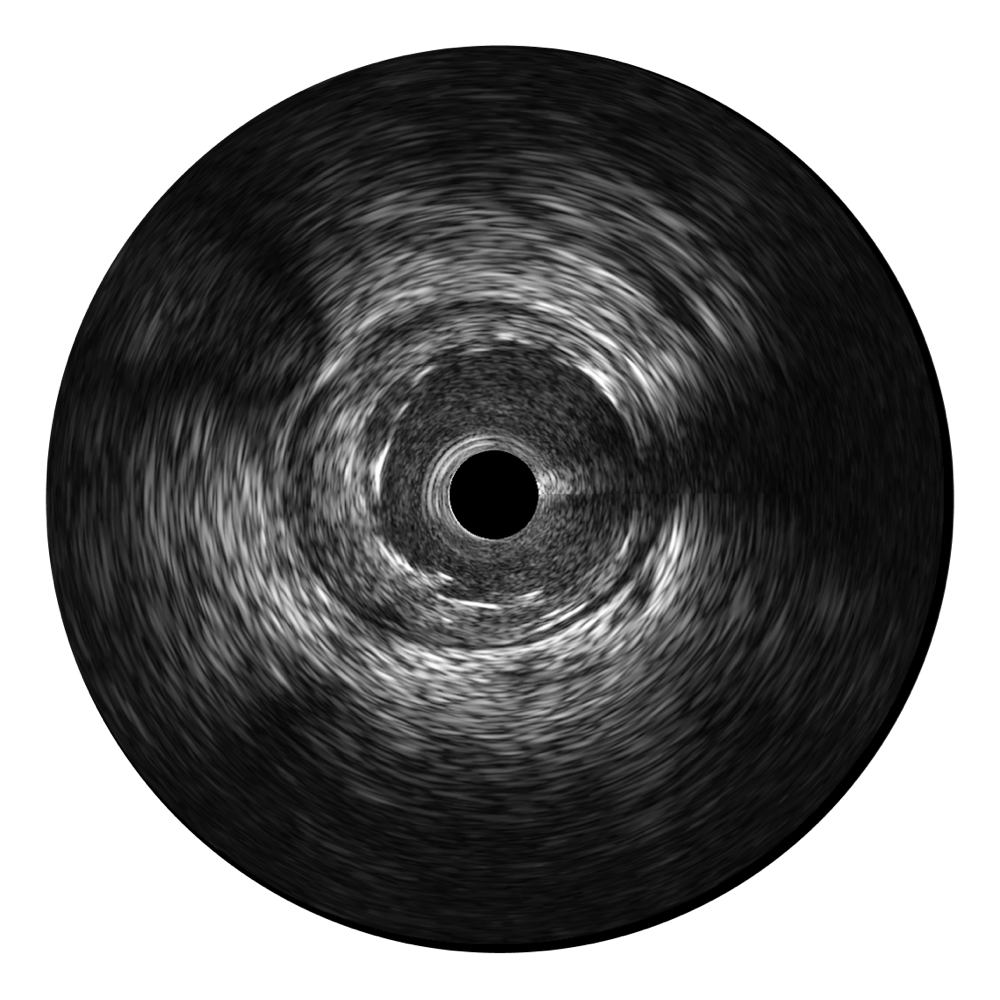

银河集团官网宽频IVUS图像

传统IVUS图像

对比传统IVUS导管成像,银河集团官网宽频IVUS图像的近场支架梁显影更细腻,远场中膜外血管仍清晰可辨,兼顾远中近,兼顾分辨力与穿透深度